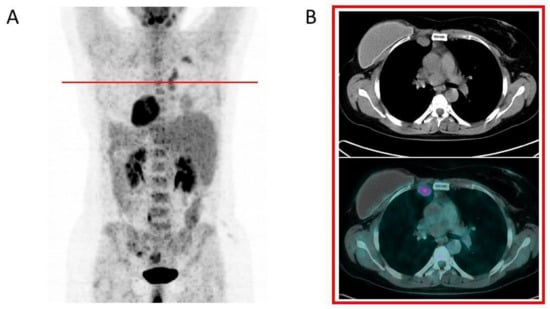

| [18F]FDG PET/CT | -No uptake or only faint uptake around the breast implant. -No axillary lymph node uptake, or just faint uptake in normally-sized nodes, vascular hilum well-visible. | -Focal uptake around the implant and in axillary, mediastinal (usually internal mammary), and supraclavicular enlarged lymph nodes; -Pericapsular fluid collection may be present, with detectable faint activity; -Fluid effusion between the breast implant and the host fibrous capsule causing asymmetry and swelling of the breast can be a sign of breast implant-associated anaplastic large-cell lymphoma. | Even bearing in mind the clinical history of each patient, both visual and semiquantitative analysis (SUVmax) do not discriminate among inflammation, infection, and neoplastic foci, because they take up glucose similarly. The clinical setting of each focal uptake (implantation for oncological versus aesthetic reasons) and any morphological findings (see above) may lead the clinician to follow-up or to collect a biopsy specimen, and eventually fluid culturing, to rule out granuloma/infection versus node metastases or lymphoma or SCC associated with breast implants. |